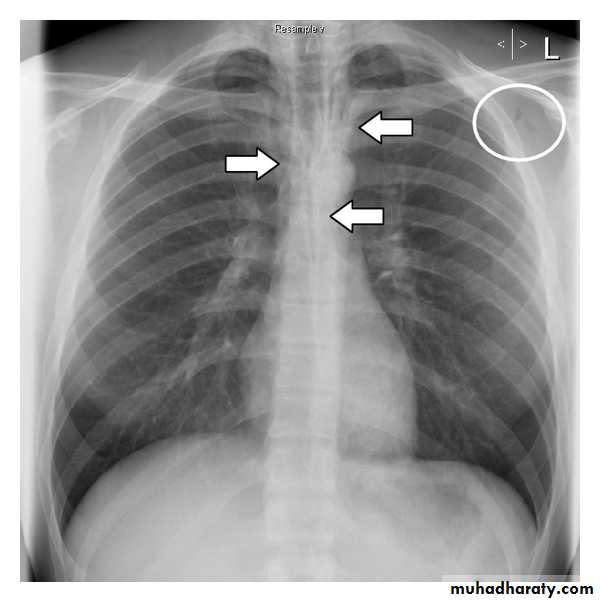

A pneumothorax is, when looked for, usually relatively easily appreciated. Typically they demonstrate:

visible visceral pleural edge see as a very thin, sharp white line

no lung markings are seen peripheral to this line

the peripheral space is radiolucent compared to adjacent lung

the lung may completely collapse

the mediastinum should not shift away from the pneumothorax unless a tension pneumothorax is present